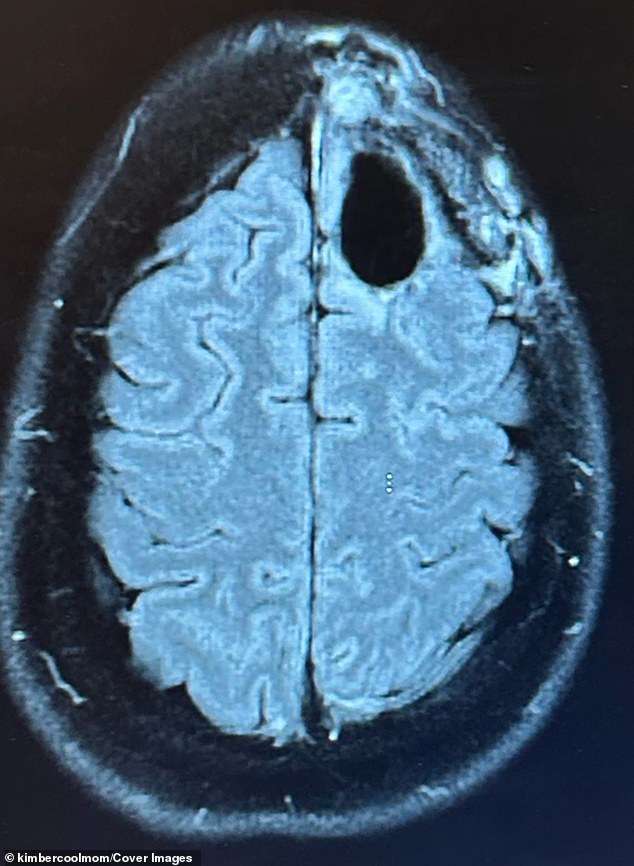

In August 2022, an MRI revealed a lime-sized mass in Pelling's frontal lobe. A biopsy confirmed her diagnosis, a cancer with a median survival rate of about 31 months. A former teacher and avid runner, Pelling believed she had done everything right. Yet the tumor, relentless and unyielding, seemed to defy all odds. She endured the standard treatments for aggressive cancers: chemotherapy, radiation, and brain surgery. The regimen left her bedbound, battling hair loss, fatigue, and brain fog. Eight months later, the cancer had progressed, forming a new, inoperable tumor. Her prognosis was slashed from three years to one.